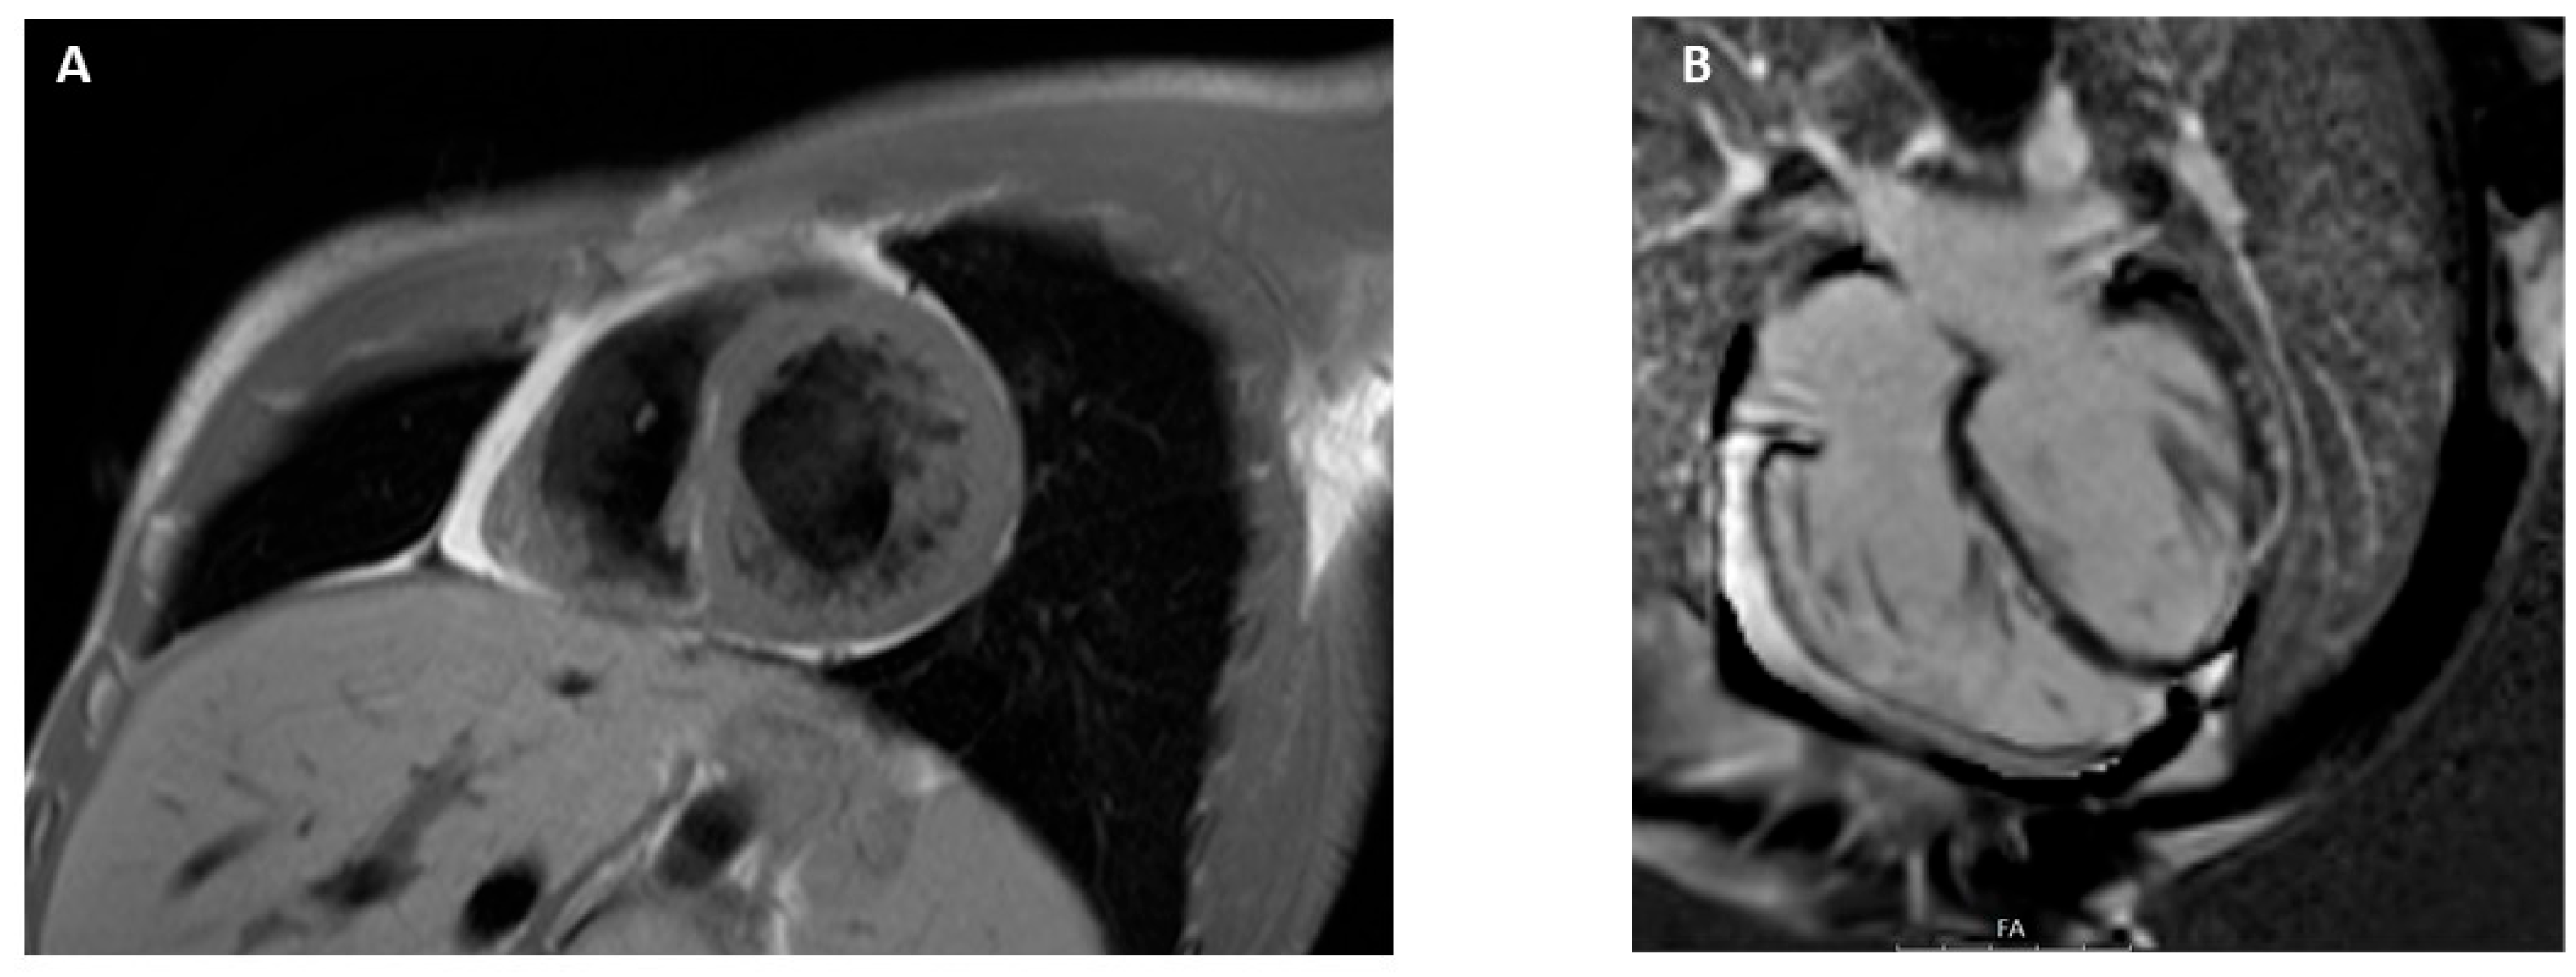

3.9. Arrhythmogenic Cardiomyopathy

- Corrado, D.; Link, M.S.; Calkins, H. Arrhythmogenic Right Ventricular cardiomyopathy. Engl. J. Med. 2017, 376, 61–72. [Google Scholar] [CrossRef]

- Corrado, D.; van Tintelen, P.J.; McKenna, W.J.; Hauer, R.N.W.; Anastastakis, A.; Asimaki, A.; Basso, C.; Bauce, B.; Brunckhorst, C.; Bucciarelli-Ducci, C.; et al. Arrhythmogenic right ventricular cardiomyopathy: Evaluation of the current diagnostic criteria and differential diagnosis. Eur. Heart J. 2020, 41, 1414–1429. [Google Scholar] [CrossRef] [PubMed]

- Corrado, D.; Perazzolo Marra, M.; Zorzi, A.; Beffagna, G.; Cipriani, A.; De Lazzari, M.; Migliore, F.; Pilichou, K.; Rampazzo, A.; Rigato, I.; et al. Diagnosis of arrhythmogenic cardiomyopathy: The Padua criteria. Int. J. Cardiol. 2020, 319, 106–114. [Google Scholar] [CrossRef]

- Aquaro, G.D.; De Luca, A.; Cappelletto, C.; Raimondi, F.; Bianco, F.; Botto, N.; Lesizza, P.; Grigoratos, C.; Minati, M.; Dell’Omodarme, M.; et al. Prognostic value of magnetic resonance phenotype in patients with arrhythmogenic right ventricular cardiomyopathy. J. Am. Coll. Cardiol. 2020, 75, 2753–2765. [Google Scholar] [CrossRef] [PubMed]